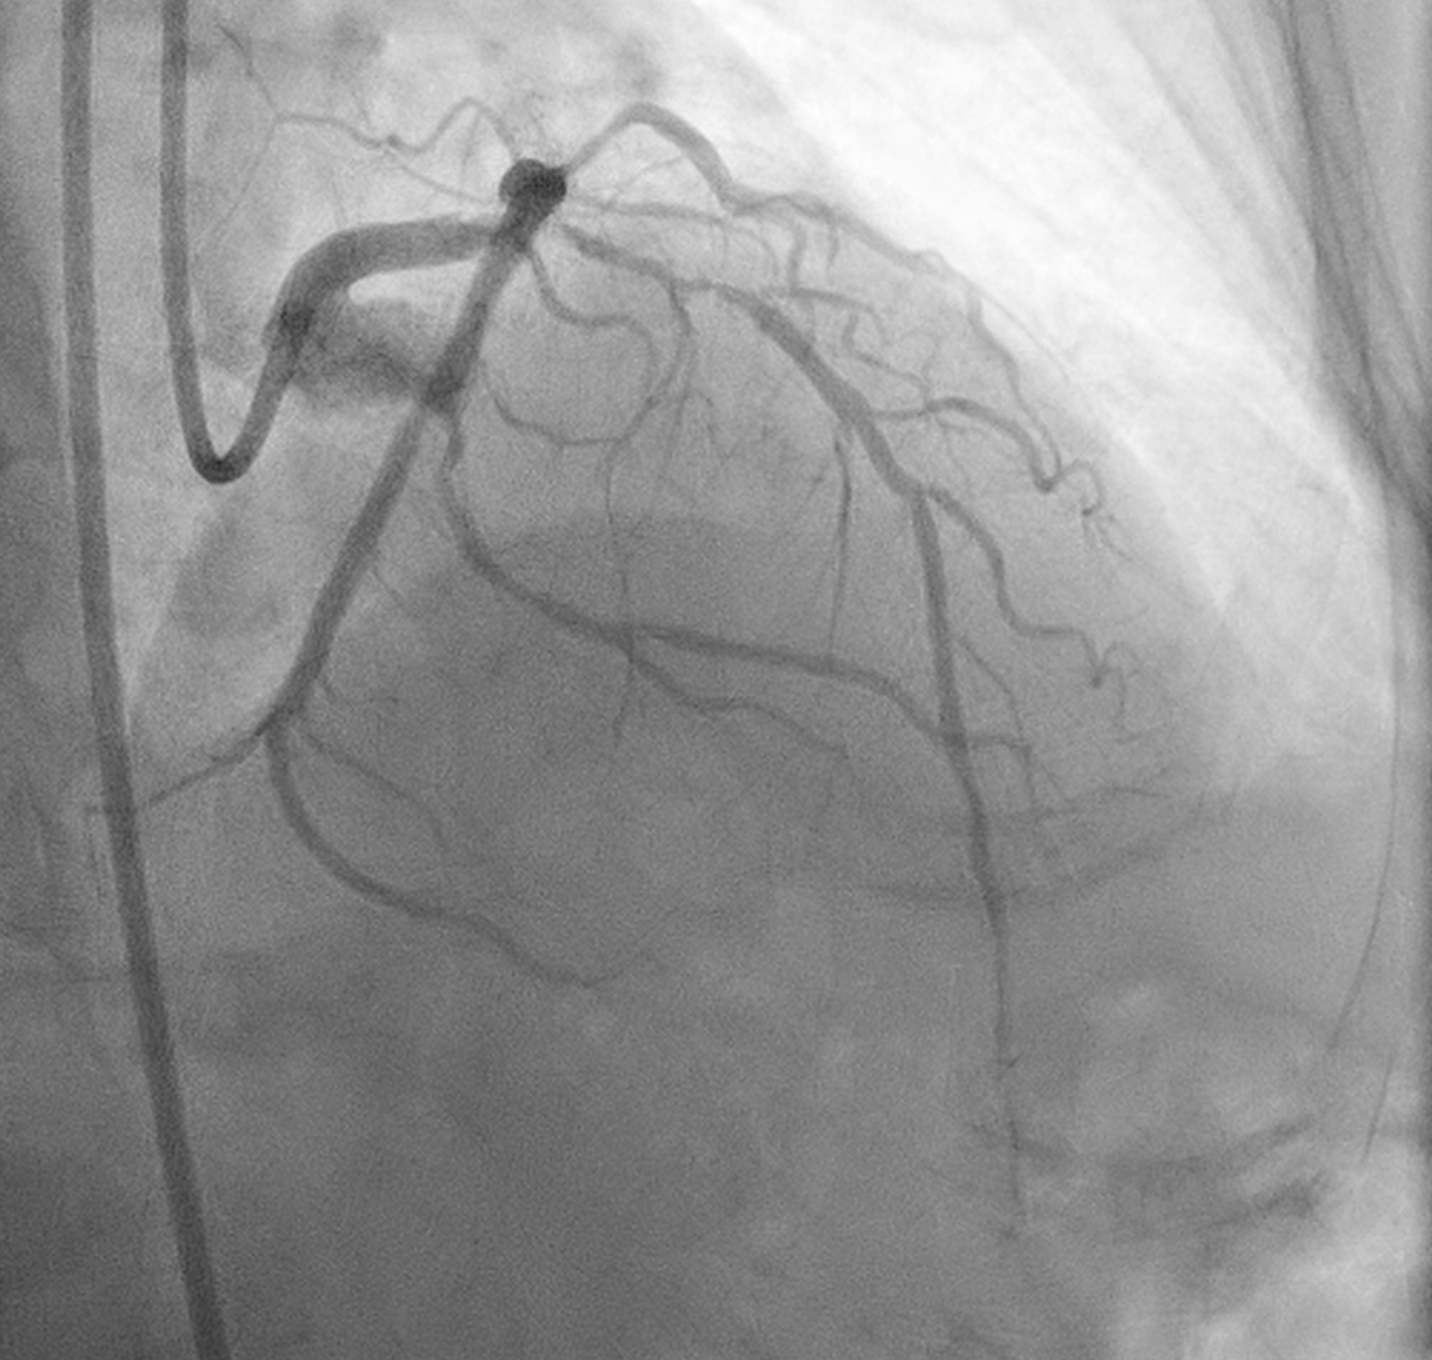

Angiography showed small non-dominant RCA with proximal severe stenosis, Left Main with severe tubular calcified stenosis at distal segmen, bifurcation lesion (medina1-1-1), LAD with diffuse calcified subtotal stenosis from ostial–mid, and LCX iwth severe tubular calcified stenosis at ostial.

Procedure was done via Right femoral artery using 7F sheath (later exchanged for a 7F long sheath due to vessel tortuosity). The left coronary artery was cannulated using a 7F EBU 3.5 guiding catheter.

PCI was initiated with Full Dose Heparin. LAD wired with Runthrough NS Floppy; predilatation with 2.0 ¡¿ 15 mm SC balloon. IVUS failed to cross proximal LAD, showing nodular calcium. Rotational atherectomy was performed using Rotapro 1.75 mm burr (180,000 rpm, four runs) followed by one polishing run at 150,000 rpm. Chest pain and ST elevation occurred shortly after rotablation due to Type F dissection in distal LM (TIMI 0 LAD). Bailout stenting with Promus Premier 3.5 ¡¿ 38 mm from LM–LAD was performed using jailed-balloon technique, followed by post-dilatation and IVUS optimization.